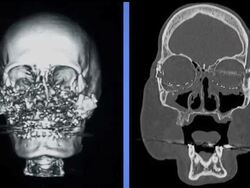

The woman who underwent the nation's first face transplant at the Cleveland Clinic is now speaking out to encourage people to become organ donors.

HEADLINE: First face transplant patient, organ donor champion

CAPTION: The woman who underwent the nation's first face transplant at the Cleveland Clinic is now speaking out to encourage people to become organ donors. (Sept. 15)